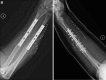

Treatment of a segmental defect in open radial and ulnar shaft fractures using rhBMP-2 and iliac crest bone graft: a case report